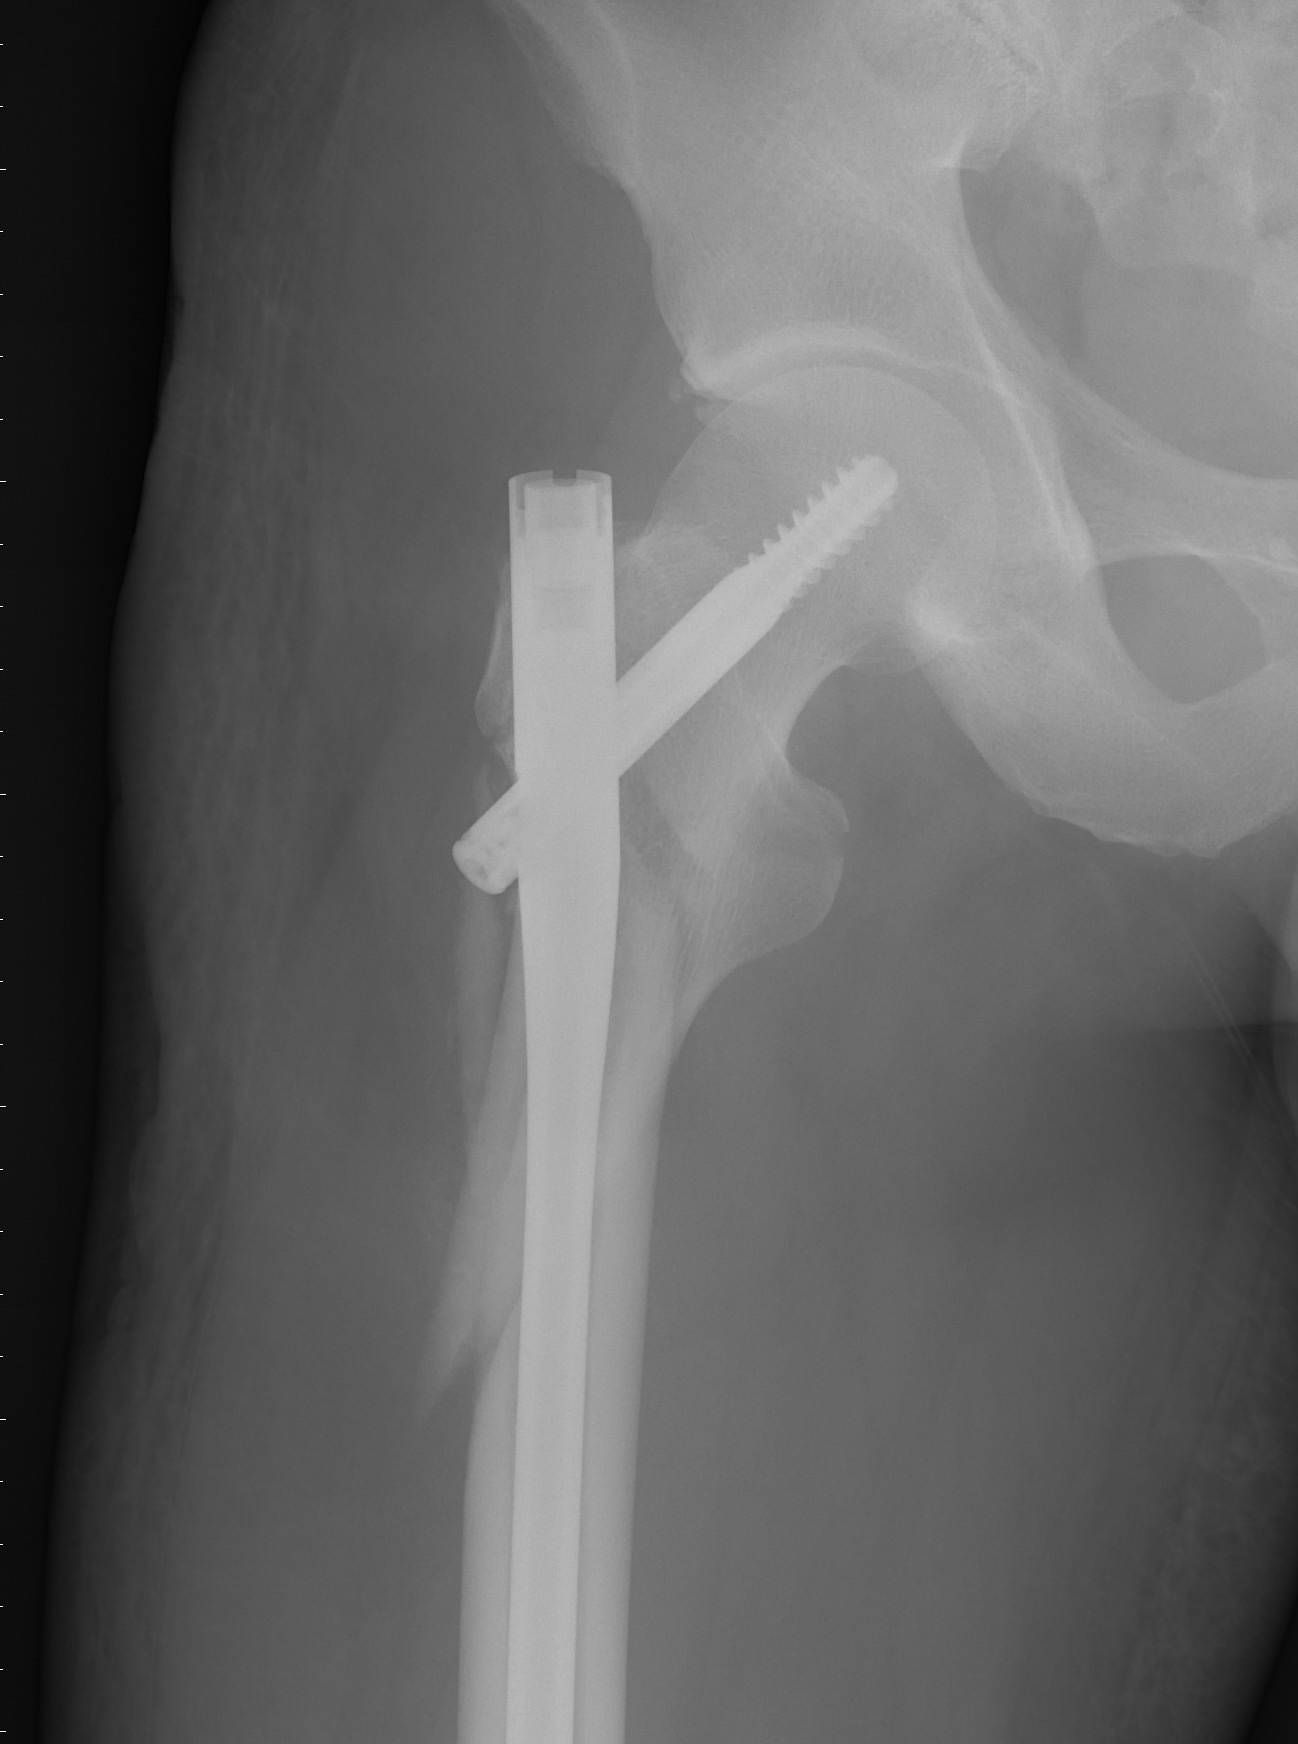

“这例手术的难点和关键点在于精确复位。患者股骨近端粉碎骨折,该部位恰好是腿部肌肉附着处,骨折移位明显,复位非常困难。而患者患有糖尿病,也为术中的麻醉控制,及术后的伤口愈合产生影响。”潘勇卫医师介绍到。3月6日,潘勇卫联合赵喆、付立功医师,为唐先生行腿部牵引、复位,并成功置入髓内钉固定。术后3天,唐先生已经可以在家人的搀扶下下床走路了,“老潘又救了我一次。”唐先生说。

图为术后X光片,竖向植入骨腔的长钉长达36公分